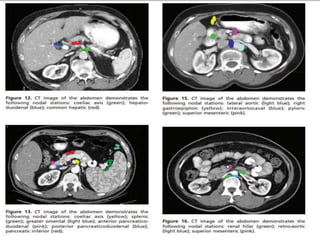

Extent of lymphadenectomy

Japanese Research Society for the study of Gastric Cancer

 N1 : LN stations 1-6 (perigastric LN)

 N2 : LN stations 7-11 (extra perigastric LN)

 N3 : LN stations 12-14 (hepatoduodenal LN)

 N4 : LN stations 15-16 (paraaortic LN)

 Removal and analysis of at least 15 LNs is required.

Lymph Node Dissection

D1- removal of involved proximal and distal stomach with

margin or total gastrectomy along with removal of lesser and

greater omental lymph nodes

(Includes right and left cardiac lymph nodes, right gastric

artery and supra and infra pyloric nodes)

D2 – D1 plus removal of all nodes along left gastric artery,

common hepatic artery, celiac artery, splenic hilum and artery

D3 – D2 plus omentectomy, clearance of porta hepatis lymph

nodes and para-aortic lymph nodes, splenectomy,

pancreatectomy.